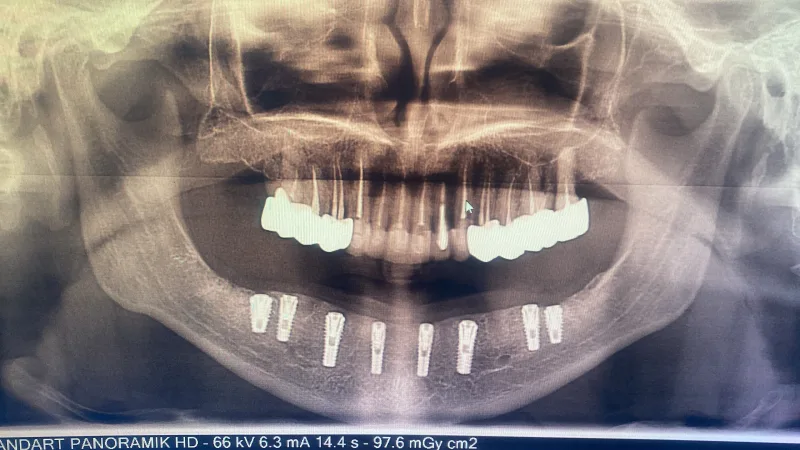

✅ Prothetik und Implantation von Zähnen